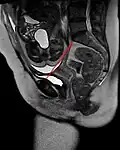

Conjugata vera as measured on sagittal MRI -